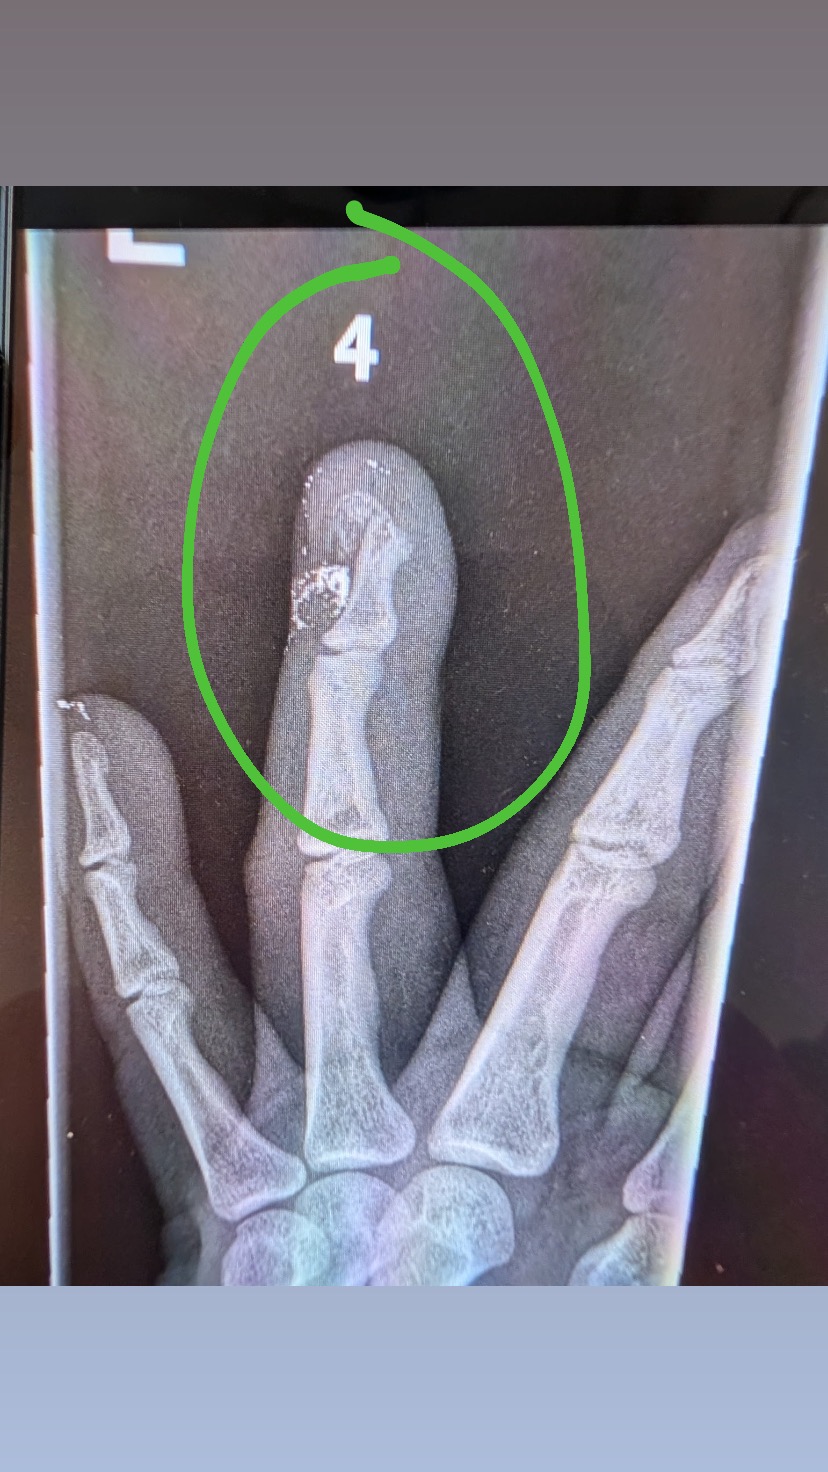

My name is Mario, and I am an independent media journalist dedicated to covering important events in our community. Recently, while reporting on a protest in front of the federal building in downtown Los Angeles, I was shot by a federal agent with a less lethal round. The impact broke my finger, and now I am facing surgery and a recovery period that will keep me out of work for an unspecified amount of time.